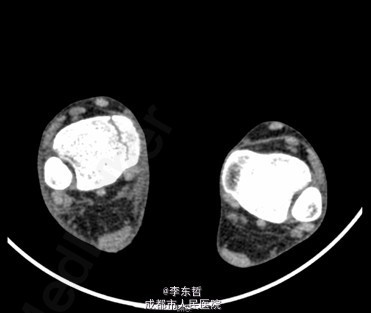

患者女,13岁4月,因“车祸致右足跟部皮肤撕脱伤清创缝合术后25天”入院。患者25天前因车祸导致右足疼痛流血伴功能障碍,右足跟部皮肤撕脱,遂到当地医院就诊,诊断为右足跟部皮肤严重剥脱伤,右跟骨骨折,右胫骨远端骨折。急诊下行“右足跟部皮肤严重剥脱伤清创缝合术”。术后给予止痛、消肿、预防感染等对症处理,目前右足外侧及跟部皮肤变暗,坏死。患者为进一步诊疗,故请我院远程会诊后转入我科继续治疗。患者病来精神、饮食可,大小便正常,体重未见明显改变。

查体:右足内踝、外踝及跟部皮肤变暗,部分缺血坏死。未见畸形,稍肿胀。触:右足趾皮温无明显降低,右足趾感觉未见明显异常。右足内踝、外踝及跟部皮肤局部压痛。动量:右踝关节活动受限,右踝关节活动诱发疼痛。右膝关节活动未见明显异常。 辅助检查:X线示:右跟骨骨折,右胫骨远端骨折。

初步诊断:1、右足跟部皮肤软组织撕脱伤清创缝合术后皮肤软组织大面积坏死伴感染;2、右跟骨骨折;3、右胫骨远端骨折;4、右足跖屈畸形。 处理:1、向患者及家属交待病情及注意事项。2、向上级医生汇报患者病情。3、完善相关术前等检查,择期行手术治疗。4、给予对症支持治疗。5、密切观察病情变化,根据病情及时处理。